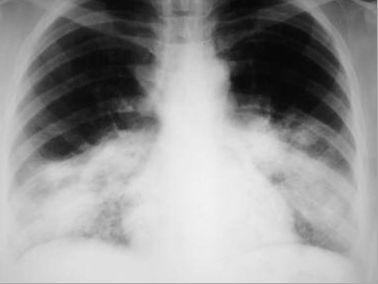

相关图片